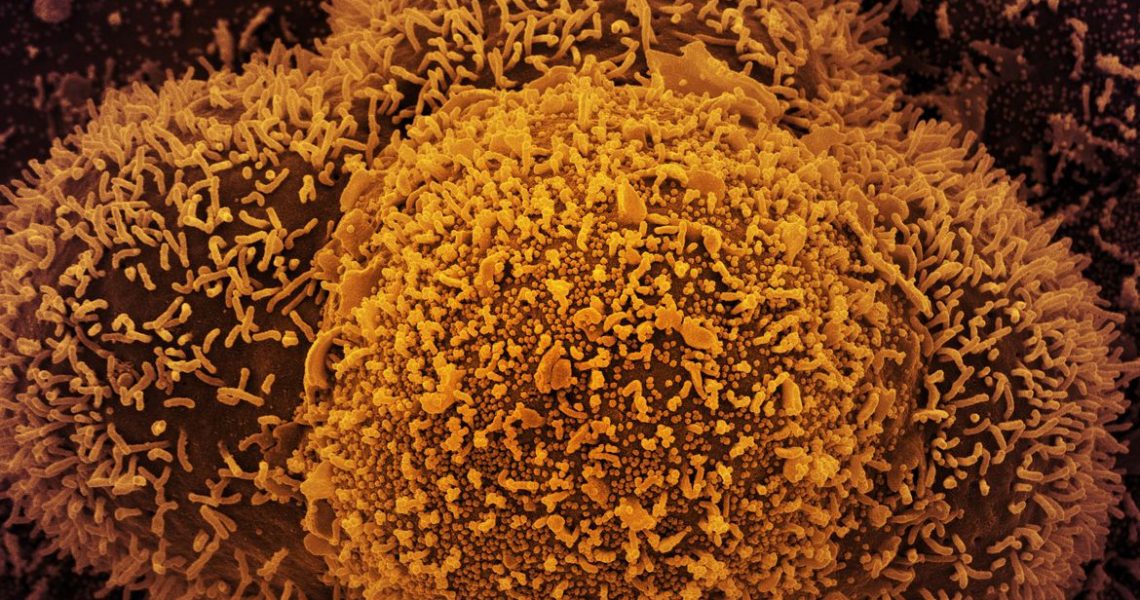

Fiocruz confirma casos da linhagem BA.2 da variante Ômicron

Dois casos foram detectados no Rio de Janeiro e em Santa Catarina A Fiocruz identificou, a partir da técnica de sequenciamento genético, dois casos da linhagem BA.2 da variante Ômicron, nos estados do Rio de Janeiro e de Santa Catarina, conforme divulgado pelas secretarias